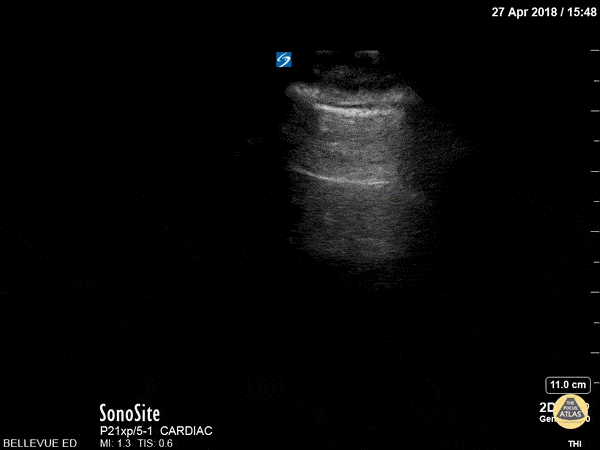

This is a clip demonstrating lung sliding. The most superficial hyperechoic layers are the soft tissue and muscular layers of the chest wall. Immediately deep to that is a bright, thin hyperechoic line which appears to be in motion - this is the pleural line. The parietal pleura rubbing against the visceral pleura as the patient breathes creates this shimmery appearance of lung sliding, also often described as “ants marching”. Lung sliding indicates that there is no pneumothorax. Hannah Kopinksi and Dr. Lindsay Davis - NYU Emergency Medicine